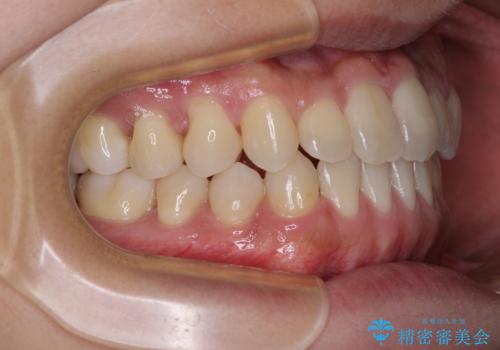

前歯のクロスバイトをワイヤー矯正で 結婚式までに治したい

- 前歯のクロスバイトを気にして来院された患者様です。

1年半後に結婚式が控えているとのことで、ワイヤー矯正で早めに治療を終えることを希望されました。

骨格的に下顎が前方に位置していましたが、歯列矯正で改善できると判断し、ワイヤー装置にて矯正治療を行うこととしました。

骨格的な左右差も顕著であったため、正中は合わず、上下前歯の一部が接触しない咬み合わせとなることが予想されましたが、正中はもともとのズレが小さかったことから、合わせることができました。